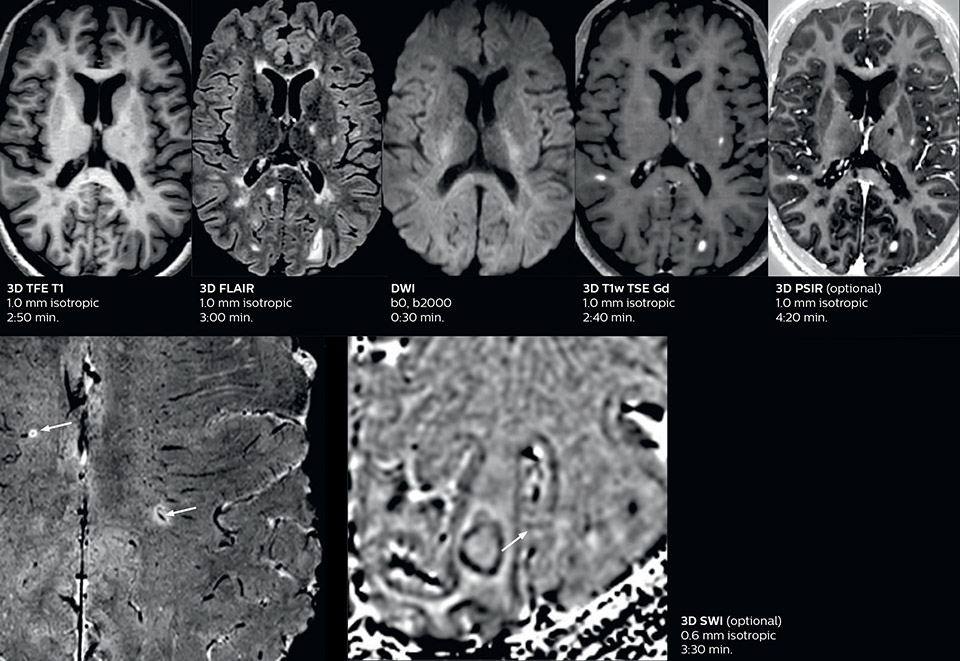

The abbreviated MS protocol for brain is only around 9 minutes, so in case of suspected multiple sclerosis, one or two more advanced sequences may be added, such as PSIR (phase sensitive inversion recovery) or susceptibility-weighted sequences to help us make more confident diagnoses in these inflammatory cases.

In this example, the optional 3D multishot susceptibility weighted sequence with 0.6 mm isotropic voxels is 2 lesions with a central vein sign (arrows) and one lesion with a phase-rim sign (arrowhead). The total scan time, including SmartBrain and axial PD/T2 3mm, is 11:10 min. and is 18:30 min. with the optional 3D PSIR and 3D SWI multishot included.

“We used to have long examination times for certain types of patients, a few lasting more than 40 minutes,” says Dr. Savatovsky. “What is remarkable, is that now all these examinations are below 30 minutes, which opens up opportunity to add more sequences when needed. It’s really hard to keep a patient for more than 40 minutes in the scanner, but because we have now cut scan times by at least 10 minutes, we can add more sequences without making the exam too long. And this is where the new system helps us make a difference. Examples include our examinations for informing brain tumor classification or giant cell arteritis workup, or for intracranial wall imaging – so in patients where we need several advanced sequences or high resolution sequences.” “We added three additional sequences in our brain neoplasm classification exam: a 3D SWI sequence, APT and ASL on top of 3D morphologic sequences, an isotropic DSC (dynamic susceptibility contrast) and multivoxel spectroscopy. I think that in patients that need a classification for brain mass, for example, we can provide a more detailed and confident diagnosis than before, allowing the clinicians to decide for either a medical workup if no tumor is suspected, or for neurosurgery as soon as possible if a neoplasm is suspected.” “In multiple sclerosis patients, we increasingly include a multishot susceptibility sequence [3] in our routine cases, thanks to the shorter scan times. Our abbreviated MS protocol for brain is around 8 to 9 minutes, so we can ask for one or two additional sequences to visualize the central veins, or to get an additional contrast to better depict posterior fossa lesions. In cases of white matter lesions of unknown significance on FLAIR images, for example when we see high signal hyperintensities in the brain, we can add on more advanced sequences such as PSIR (phase sensitive inversion recovery) or susceptibility-weighted sequences to help us in distinguishing between MS and nonspecific or vascular abnormalities in these inflammatory cases.”